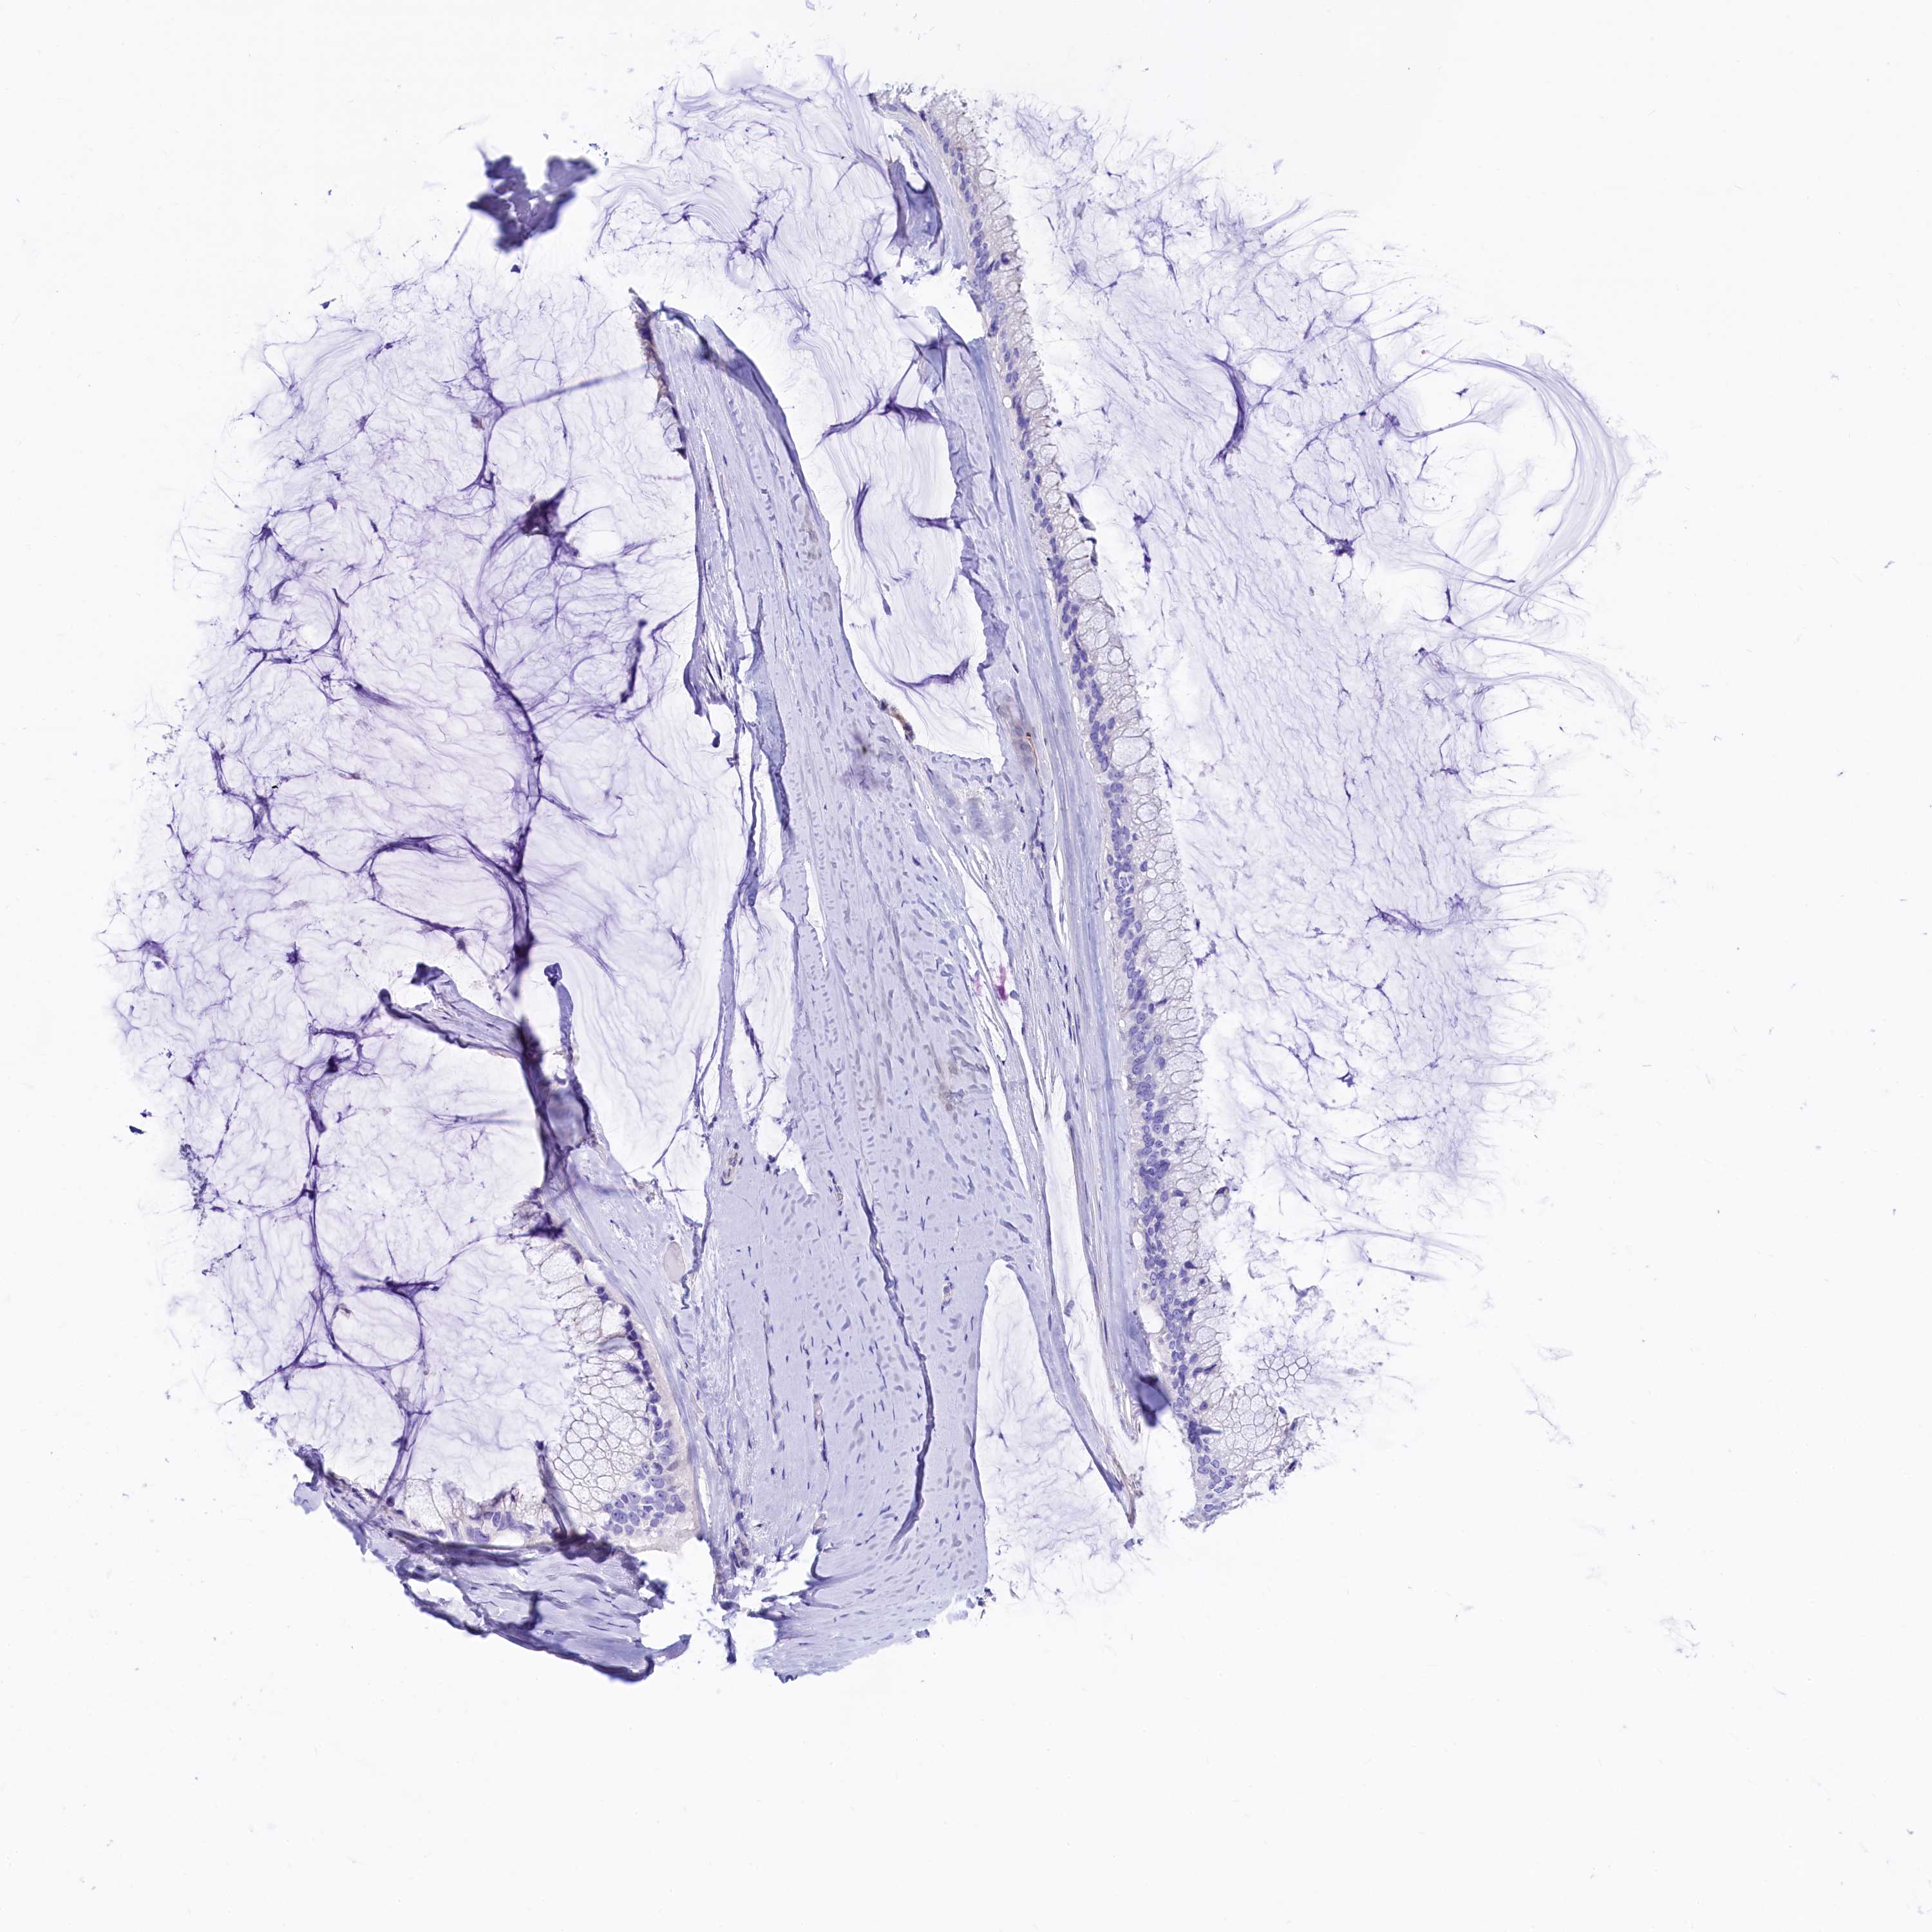

OVARIAN CANCER - Protein expressioni

A mouse-over function shows sample information and annotation data. Click on an image to view it in a full screen mode. Samples can be filtered based on level of antibody staining by selecting one or several of the following categories: high, medium, low and not detected. The assay and annotation is described here.

Note that samples used for immunohistochemistry by the Human Protein Atlas do not correspond to samples in the TCGA dataset.

Antibody stainingi

Antibody staining in the annotated cell types in the current human tissue is reported as not detected, low, medium, or high, based on conventional immunohistochemistry profiling in selected tissues. This score is based on the combination of the staining intensity and fraction of stained cells.

Each image is clickable and will lead to virtual microscopy that enables deeper exploration of all samples and also displays staining intensity scores, fraction scores and subcellular localization as well as patient and tissue information for each sample.

Antibody HPA041301

Antibody HPA044239

Staining

High

Medium

Low

Not detected

Intensity

Strong

Moderate

Weak

Negative

Quantity

>75%

75%-25%

<25%

None

Location

Nuclear

Cytoplasmic/membranous

Cytoplasmic/membranous,nuclear

Cystadenocarcinoma, serous, NOS

Carcinoma, endometroid

Cystadenocarcinoma, mucinous, NOS

Carcinoma, NOS